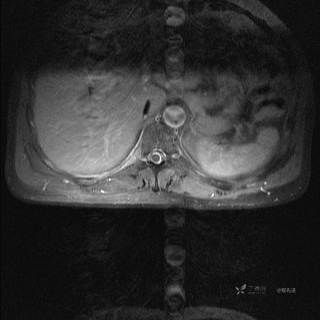

MR

T2

T2压脂

T1

T1增强

T1增强冠状位

T1增强横断位